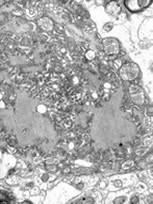

This species Coccidia is an opportunistic single cell parasite that affects the digestive system. Like worms this parasite is often detected by fecal exam. Unlike worms however these parasites never grow large enough to be seen by the naked eye. The Coccidia is also known in its initial state as an Oocysts (pronounced o'o-sists), which can easily be visualized as a little “o” inside of a big “O” as seen through the microscopic picture.